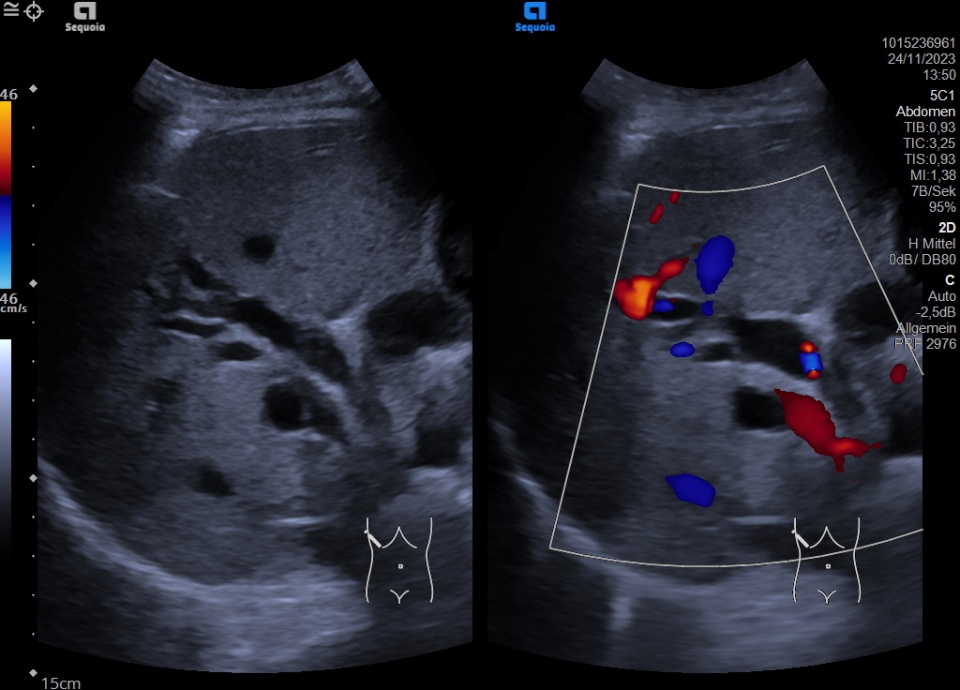

Cholestasis Atlas of Ultrasound

Cholestasis Atlas of Ultrasound Cholestasis Ultrasound Findings the term cholestasis is commonly referred to an impairment of. cholestasis represents an impaired secretion of bilirubin by hepatocytes, manifesting with high blood. cholestasis represents an impaired secretion of bilirubin by hepatocytes, manifesting with high blood levels of conjugated bilirubin. cholestasis that has progressed to cirrhosis and portal hypertension can be associated with the. Cholestasis is. Cholestasis Ultrasound Findings.

Cholestasis Atlas of Ultrasound Cholestasis Ultrasound Findings the term cholestasis is commonly referred to an impairment of. Bile is the digestive fluid produced. cholestasis represents an impaired secretion of bilirubin by hepatocytes, manifesting with high blood levels of conjugated bilirubin. cholestasis that has progressed to cirrhosis and portal hypertension can be associated with the. all infants with cholestasis should undergo abdominal ultrasonography as. Cholestasis Ultrasound Findings.

Cholestasis Atlas of Ultrasound Cholestasis Ultrasound Findings cholestatic jaundice can be classified into intrahepatic or extrahepatic cholestasis,. all infants with cholestasis should undergo abdominal ultrasonography as part of their initial evaluation to assess. cholestasis represents an impaired secretion of bilirubin by hepatocytes, manifesting with high blood. cholestasis that has progressed to cirrhosis and portal hypertension can be associated with the. Cholestasis is reduction. Cholestasis Ultrasound Findings.